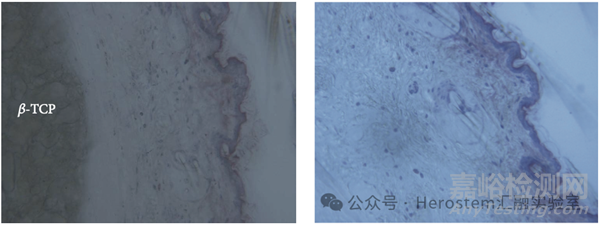

結果如上圖顯示,直徑 4mm 的 TCP-PRP 被軟組織包裹,整個植入物分布在真皮和骨骼之間;β-TCP 形成一團聚集體,不規(guī)則地分布在網(wǎng)狀真皮的整個橫截面,TCP-PRP 的分布也可以通過注射后的積極按摩來調整。β-TCP 的擴散在與皮膚垂直的方向上更加受限(即上圖右中的縱向),這可能是因為真皮細胞排列相當緊致,這也代表想要將任何含有微球的凝膠注射至真皮層是非常困難的。

TCP-PRP 被結締組織(CT)所包裹(如上圖),沒有觀察到肌成纖維細胞的誘導。沒有檢測到肉芽腫,有一些孤立的巨噬細胞隨機分布在真皮中。

下圖中,皮膚結構在形態(tài)上完好無損,注射所有 TCP-PRP 的區(qū)域都沒有引起炎癥,代表β-TCP 的惰性和生物相容性。